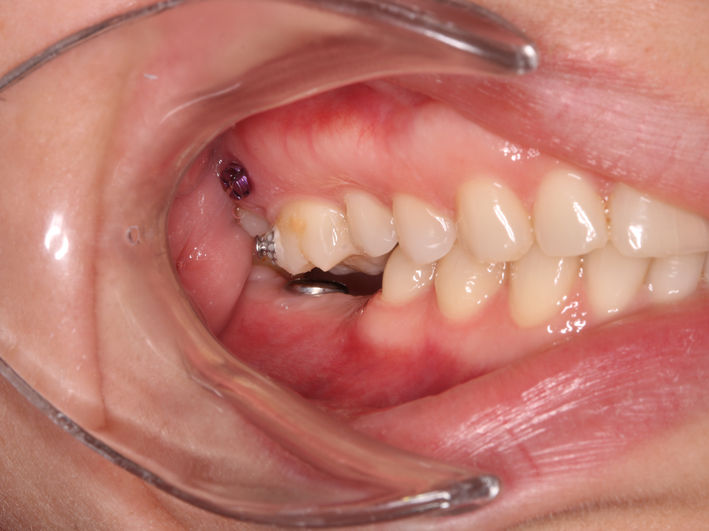

Pacienta se prezinta în cabinet pentru a trata leziunea de la nivelul molarului inferior. Analizând ocluzia observăm absența spațiului suficient pentru o lucrare corectă. Astfel, am aplicat un aparat dentar local cu mini-implanturi pentru a intruza molarul superior si a recâștiga spațiul necesar.

După tratamentul ortodontic și câștigarea spațiului necesar am preparat minim dintele, am luat amprentă și tehnicianul a realizat un onlay din material compozit. Acesta a fost lipit sub izolare cu digă.